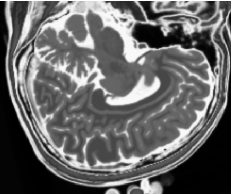

2.4 Imagens Multiespectrais Sintéticas

No estudo de caso deste trabalho foram utilizadas 1086 imagens multiespectrais sintéticas de ressonância magnética com três bandas, compostas por 3258 imagens sagitais de 1 mm de espessura, resolução de 1 mm3, ponderadas em densidade de prótons, T1subscript𝑇1T_{1} e T2subscript𝑇2T_{2}, para um cérebro humano normal, obtidas por um sistema tomográfico de ressonância magnética com níveis de ruído de 0%, 1%, 3%, 5%, 7% e 9%, e sem inomogeneidades de campo. Essas imagens foram geradas pelo simulador de RM BrainWeb, que permite a geração de imagens sintéticas de RM ponderadas em densidade de prótons, T1subscript𝑇1T_{1} e T2subscript𝑇2T_{2} variando o nível de ruído e o percentual de inomogeneidade de campo [51, 52].

As figuras 2 (banda 0), 3 (banda 1) e 4 (banda 2) mostram a fatia 97 de um volume de imagens sagitais com 181 fatias e 0% de ruído, ponderadas em PD (densidade de próton), T1subscript𝑇1T_{1} e T2subscript𝑇2T_{2}, enquanto a figura 5 ilustra a composição colorida R0-G1-B2 da mesma fatia. Pode-se notar no topo do crânio, na parte inferior das imagens, a presença de artefatos, que podem ser resultantes de erros no simulador, mas que não são prejudiciais à análise, uma vez que, neste trabalho, não é dada ênfase à análise anatômica.

Refer to caption

Figura 2: Imagem de RM da fatia 97 ponderada em PD